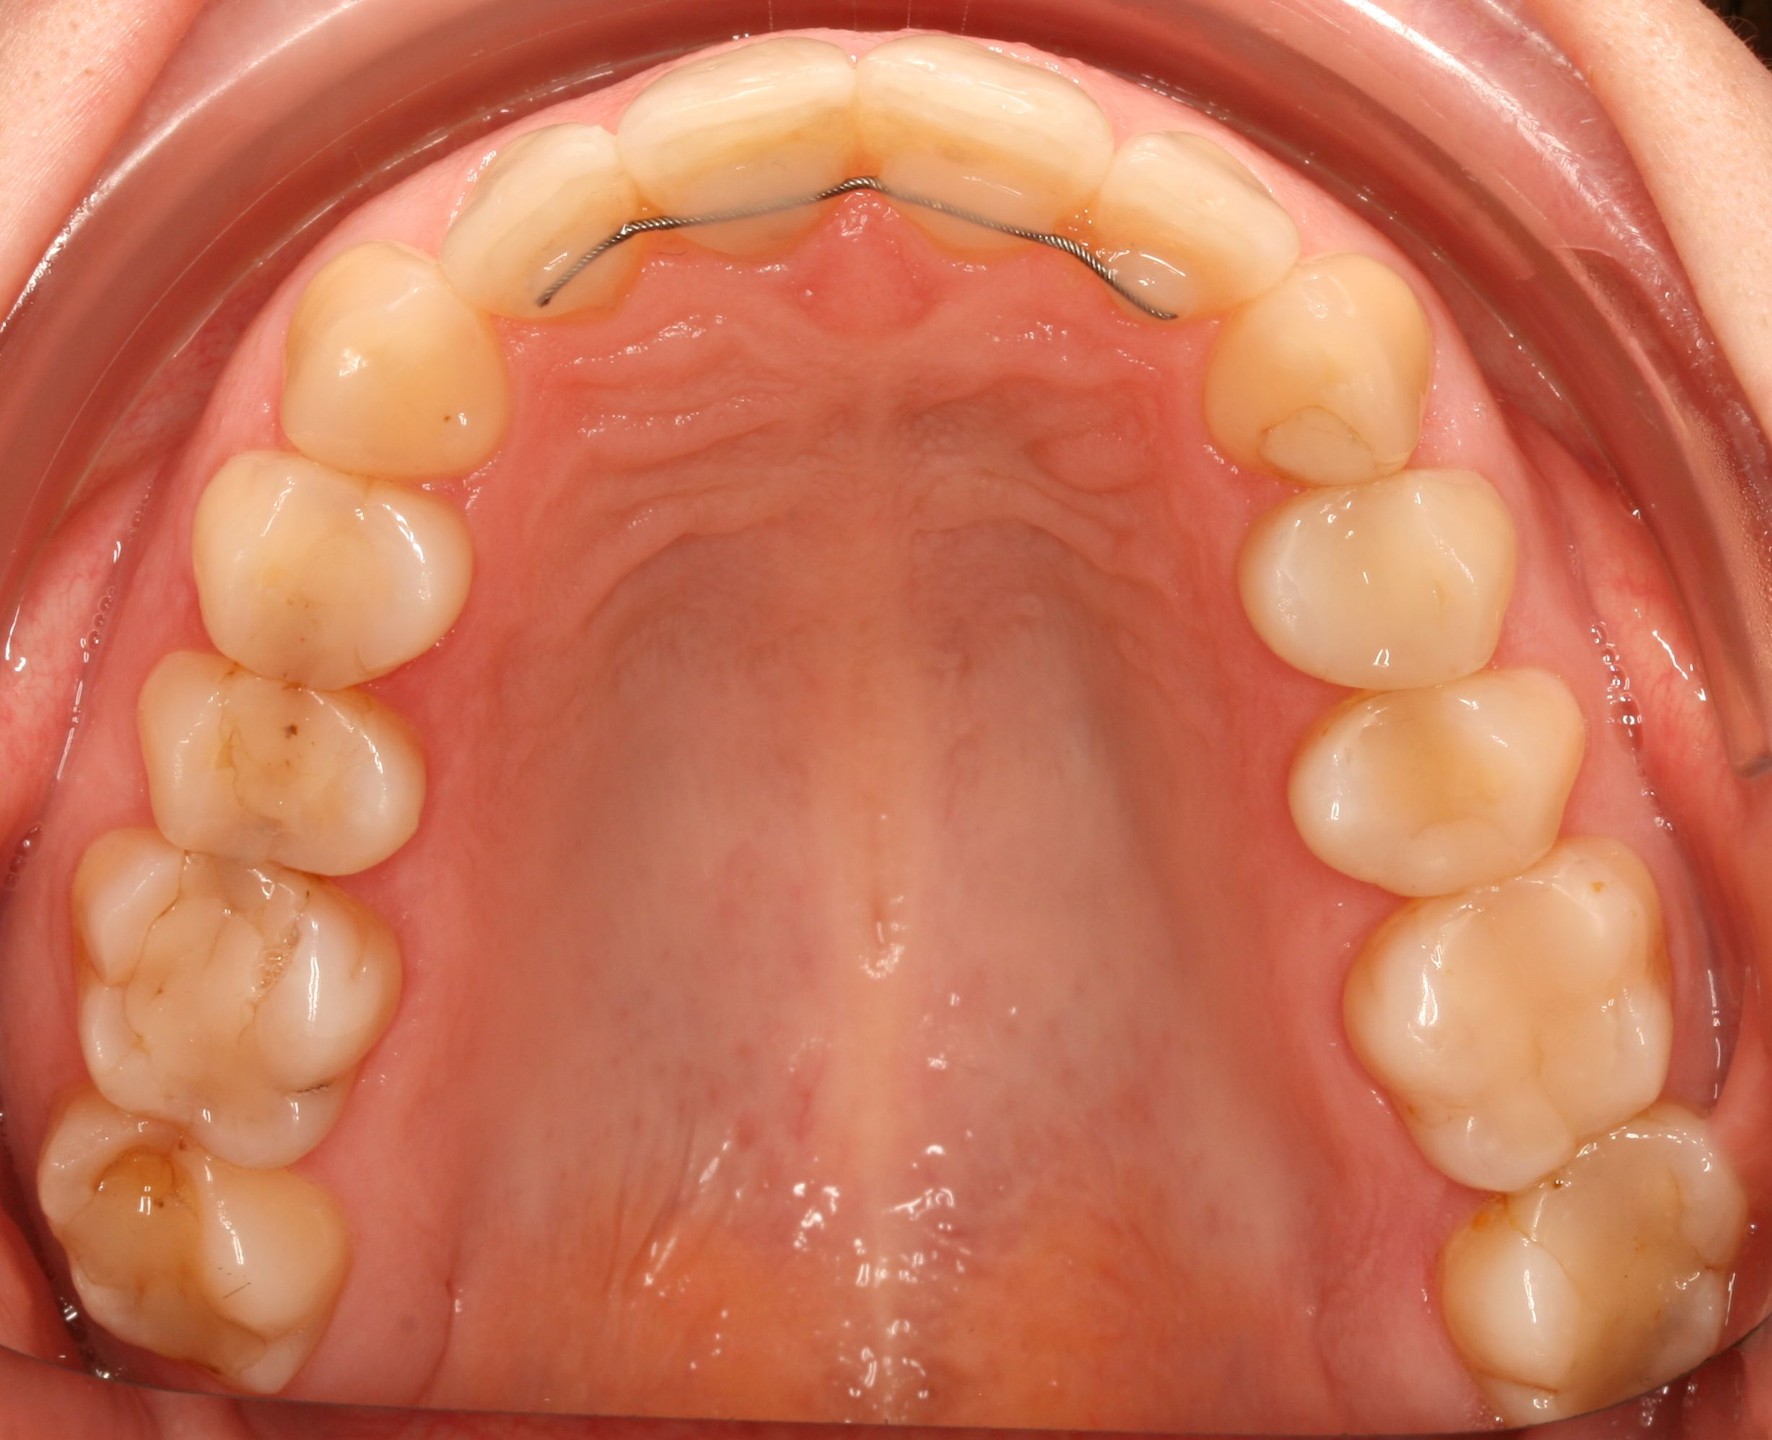

Структура зубов изнутри: фотографии и объяснения

Раздел: Фотомир